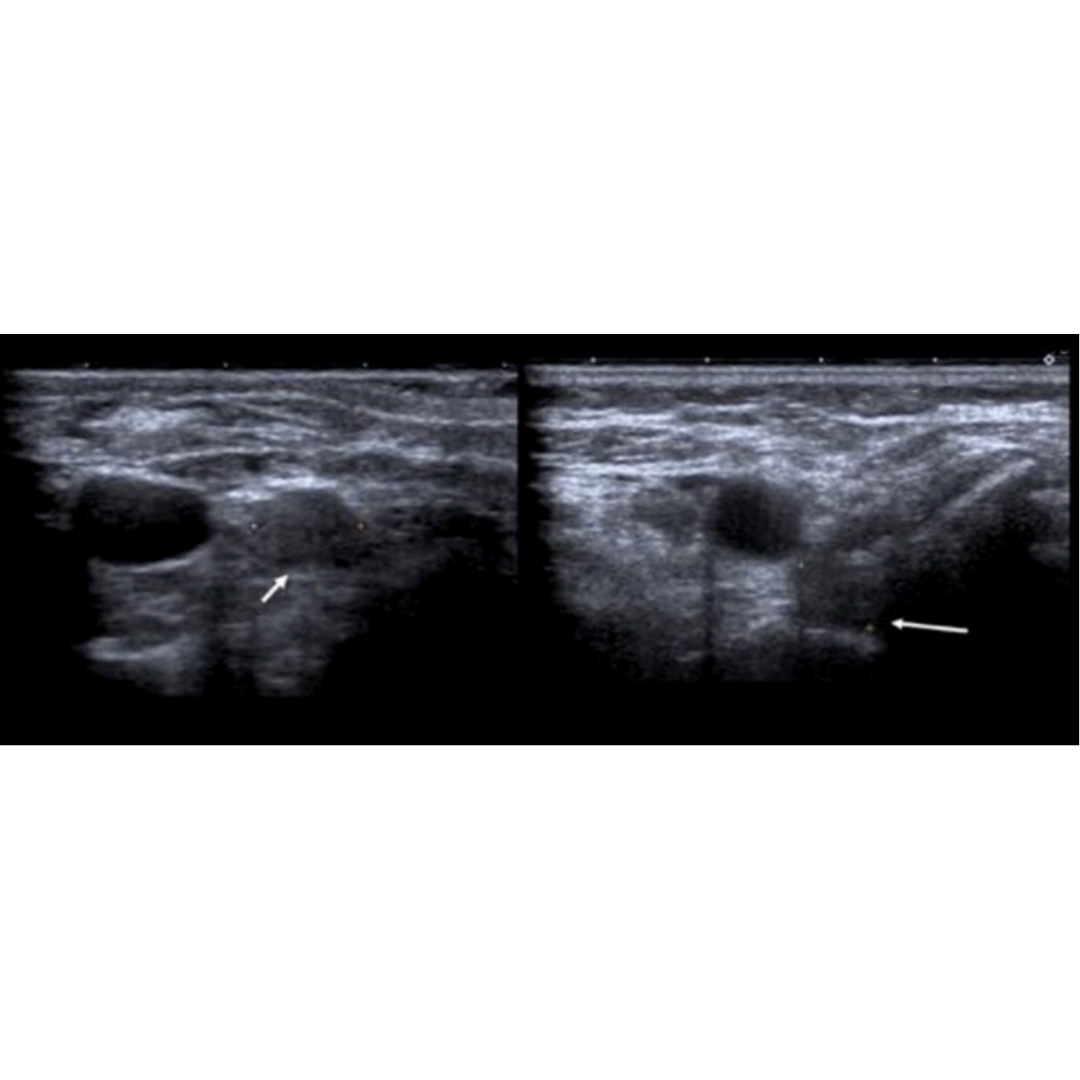

Figura 11. Ecografía de cuello en corte axial muestra características de los ganglios metastásicos. (a.) Ganglio linfático quístico con focos internos ecogénicos (flecha) que representan microcalcificaciones. No olvidar que la sombra del proceso transversal de la columna cervical (*), no debe confundirse con una calcificación de metástasis. (b.) Ganglio linfático hipoecogénico sin hilio graso.